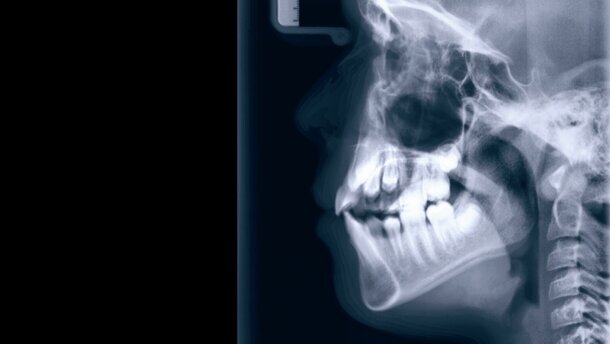

WIEN – „Das Kiefergelenk ist das wichtigste Gelenk im Körper“, schrieb Dr. George Goodheart, Begründer der Applied Kinesiology. Kaum ein kompetenter Therapeut im Bereich des Bewegungsapparates wird heute bestreiten, dass das Kiefergelenk mit seiner Arbeits- und Stützmuskulatur wichtig ist, aber dass es das wichtigste Gelenk sein soll, dürfte möglicherweise überraschen.

Seit über 40 Jahren beschäftigt sich Prof. Harold Gelb, Leiter der Pain Clinic an der Tufts University in Boston, mit dem Problem Kiefergelenk und Statik. Seine These: „Gehe von orthopädischen Idealverhältnissen und -proportionen aus und versuche, diese auch und gerade für Gesicht, Schädel, Mandibula und Kiefergelenk (wieder) herzustellen.“ Er setzte als einer der ersten die Tatsache um, dass die Stellung der Zähne und die vertikale Dimension entscheiden, wie der Condylus mandibularis in der Fossa articularis des Os temporale zu liegen kommt und dass nicht die Muskulatur und nicht das Gelenk, sondern die Stellung der Zähne – und somit die Interkuspidation (IKP) – entscheidet. Mit Kunststoffschienen auf den Unterkiefer versuchte Prof. Gelb die Körperhaltung zu beeinflussen. Der Forscher vertritt die Meinung, dass das Kiefergelenk dem Stütz- und Bewegungssystem übergeordnet ist und Störungen desselben wiederum das Kiefergelenk (Ursache und Folgekette) beeinflussen.

Da sich Kiefergelenk und Haltungsapparat gegenseitig beeinflussen, hat das auch Ein-fluss auf die zahnärztliche Bissnahme. In jeder Sekunde der Bissnahme fixiert der/ die Zahnarzt/-ärztin oder Kieferorthopäde/-in die Fehlstatik des Patienten. Deshalb sollte vor den Bissnahmen im Idealfall eine Balancierung des muskulären Systems durch eine manuelle Therapie (Chirotherapie) und/oder Osteopathie erfolgen. Bereits vor 20 Jahren konnten Kopp und Plato die Beeinflussung der Ruheschwebe des Unterkiefers durch Atlastherapie nach Arlen zeigen. Um den Behandlungserfolg durch eine Schienentherapie zu stabilisieren, ist eine begleitende Physiotherapie der Kiefer- und Halsmuskulatur unbedingte Voraussetzung.